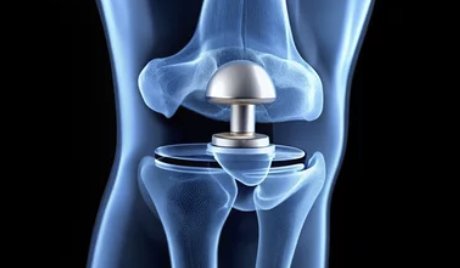

무릎 인공관절 수술은 손상된 무릎 관절을 제거하고, 이를 대신할 인공관절을 삽입하는 수술입니다. 주로 퇴행성 관절염, 연골 손상, 또는 무릎 관절의 기형으로 인해 무릎 기능이 심각하게 손상된 사람들에게 시행됩니다.

2. 인공관절의 종류

- 국산 인공관절과 수입 인공관절의 가격 차이가 큽니다. 수입 제품은 품질과 기술력이 우수할 수 있지만 가격이 더 비싸며, 국산 제품은 상대적으로 저렴하지만 품질도 우수한 편입니다.

3. 수술 방식

- 부분 인공관절 수술과 전체 인공관절 수술에 따라 비용이 다릅니다. 부분 인공관절 수술은 무릎의 일부만 교체하는 방법으로, 비용이 상대적으로 저렴할 수 있습니다. 반면에 전체 인공관절 수술은 무릎 전체를 교체하는 방법으로, 더 복잡하고 비용이 높습니다.

최근에는 무릎 인공관절 수술의 기술 발전과 함께, 환자 맞춤형 수술법이 도입되고 있습니다. 이는 수술의 정확성을 높이고, 회복 속도를 빠르게 하는 데 도움을 줍니다.

- 로봇 수술: 로봇 보조 수술이 점점 널리 사용되고 있으며, 이는 수술의 정밀도를 높여 부작용을 줄이고 회복 기간을 단축하는 데 기여합니다.

- 맞춤형 인공관절: 각 환자의 무릎 형태와 상태에 맞춰 맞춤형 인공관절이 제작되어, 환자의 활동성과 수명을 더 연장시키는 기술이 발전하고 있습니다.